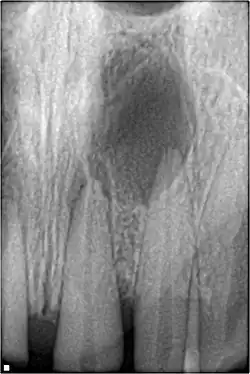

Curetage périradiculaire

L'objectif du curetage est de retirer le tissu granulomateux ou kystique et/ou les corps étrangers de l'os alvéolaire dans la région apicale ou latérale entourant une dent dépulpée. Le procédé est rarement utilisé seul, et seulement quand le système canalaire a été jugé correctement désinfecté et rempli.